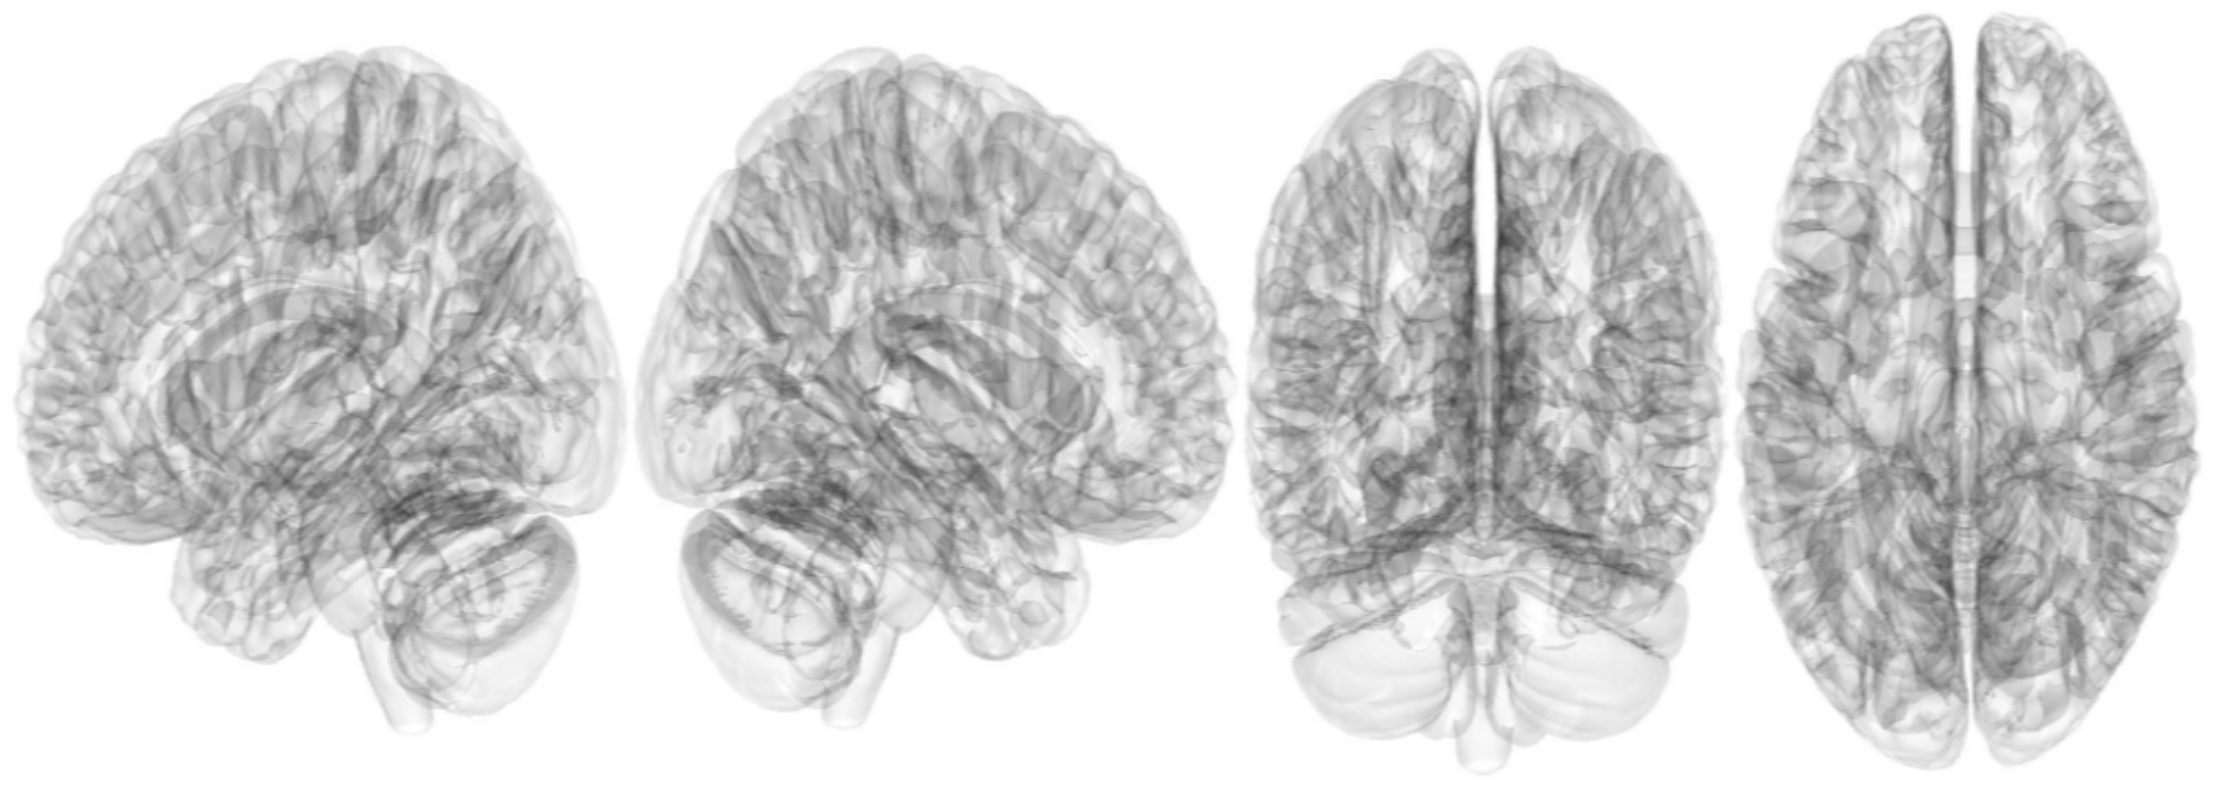

2.3. Connectometry Analysis with Statistical Analysis